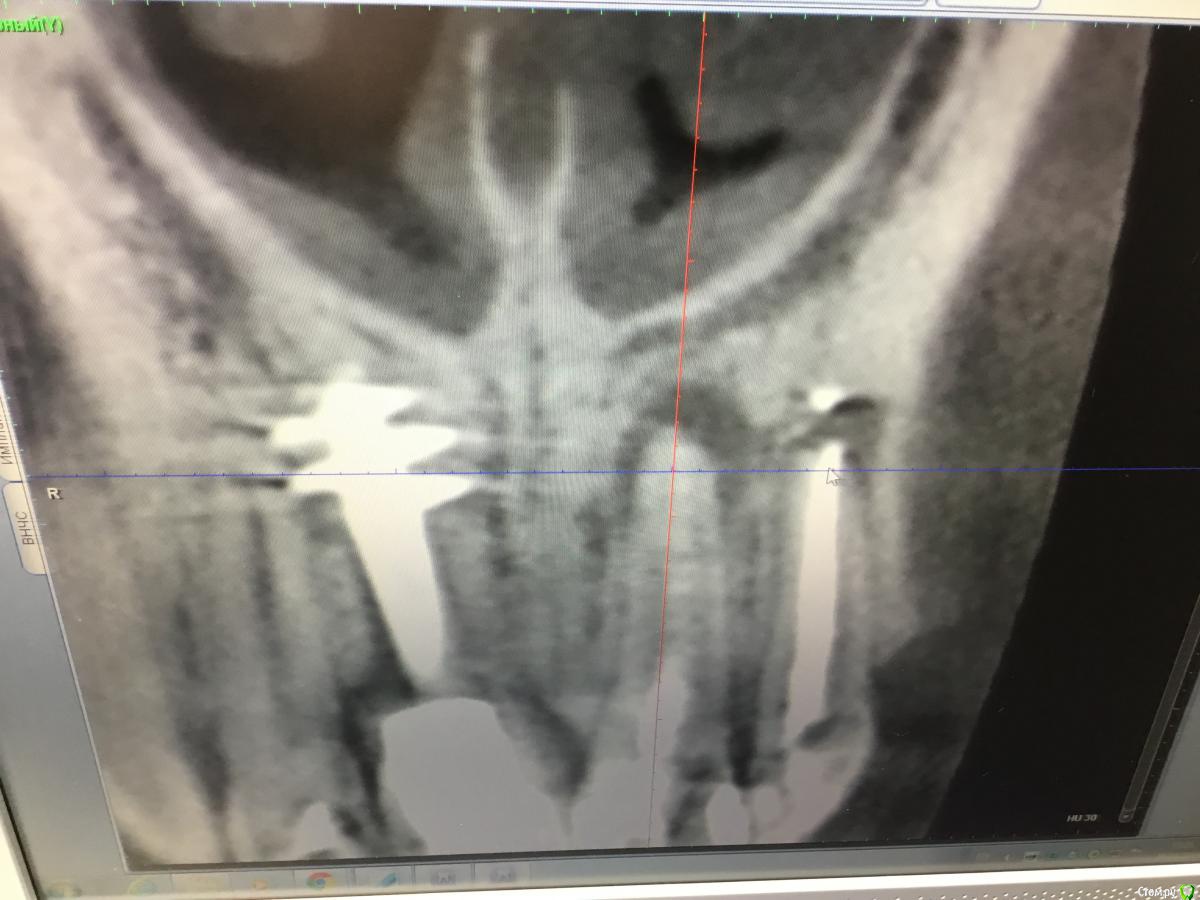

Zorrro Опубликовано 6 марта, 2016 Поделиться Опубликовано 6 марта, 2016 (изменено) Мой постоянный пациент привёл своего сынишку с жалобами на свищь на нёбе.Сделали кт и решили ,что вначале переберём каналы,а через пол года будем посмотреть куда нам двигаться дальше… Эстетика коронки на 11 вполне устраивала пациента,тем более он был уверен,что поставилимплант и вследствии коронку популярный доктор используя новейшие технологии и материалы,позволяющие не прибегать к устаревшим костным и ещё каким-то пластикам.запись к доктору уходила на пол года вперёд и молодой человек чудом втиснулся в этот плотный график,чтобы отхватить немножко и себе этих самых "новейших" технологий под нос. Фото ещё раз показывает,чтосамое главное в успехе частной практики это ВЕРА доктора в себя и то,что он делает.меня же коронка устраивала тем более,потому что переделывать её вместе с имплантом мне крайне не хотелось.обошлись комментарием про усиленную гигиену и регулярные наблюдения раз в пол года. итак занялись посильным трудом:отмыли 21 и 22,констрикция убежала за 50.02,остановились на 70.02 стальными файлами отступя 1мм,метапекс,через 2 недели irm и стекловолокно нафуджи+,филтек.договорились про контроль через пол года и коронки если всё ок. Ещё немного срезов до и преимущество кт перед прицельными снимкамиИ сразу после. Про коронки и корневой герметизм пациент не понял и решил оставить бломбы на месте. Изменено 6 марта, 2016 пользователем Zorrro 1 Ссылка на комментарий